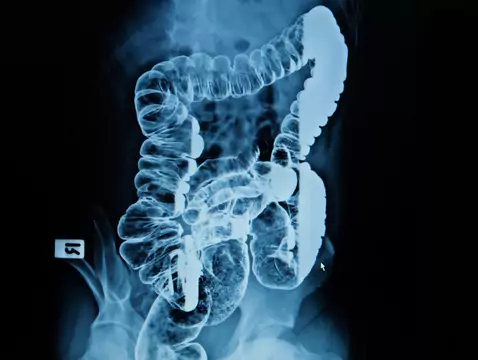

Colorectal cancer is a neoplasm occurring in: the colon, sigmoid flexure and rectum. In 90-95% of cases the incidence of colorectal cancer is sporadic, in the remaining 5-10% there is a hereditary...